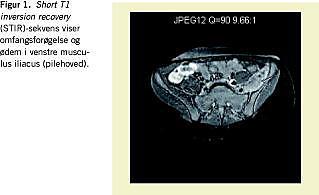

Der blev indledt behandling med intravenøs dicloxacillin 50 mg/kg/døgn. Elektrokardiogram og ekkokardiografi var normale. CRP var nu 1.329 nmol/l, mens leukocyttallet kun var 10,3 × 109 (3,0-10,0) med overvægt af granulocytter. Sedimentationsreaktionen var på 72 arb.enh. Kreatininkinase var 28 U/L (50-250). Magnetisk resonans (MR)-skanning (Figur 1 ) viste venstre musculus iliopsoas ødematøs og omfangsforøget i hele sin udstrækning. Der var ingen mistanke om absces. Normale forhold ved genitalia, hofte og sakroiliacaled. På mistanke om pyomyositis øgedes dicloxacillin til 100 mg/kg/døgn fordelt på fire doser. Efter to døgn var pigen afebril og smerterne aftagende. Ved kontrol-MR-skanning efter tre ugers behandling var de muskulære forandringer aftaget, men der var nu ansamling i venstre sakroiliacaled med omkringliggende osteomyelitforandringer. Efter samråd med Mikrobiologisk Afdeling blev antibiotika givet 11 dage intravenøst og herefter tre måneder peroralt med dosis forøgning til 120 mg/kg/døgn. Efter et halvt år var pigen tilbage på fuldt aktivitetsniveau uden sequelae. Kontrol MR-skanning viste da ingen bløddelsforandringer, men diskrete signalforandringer efter tidligere osteomyelitis.